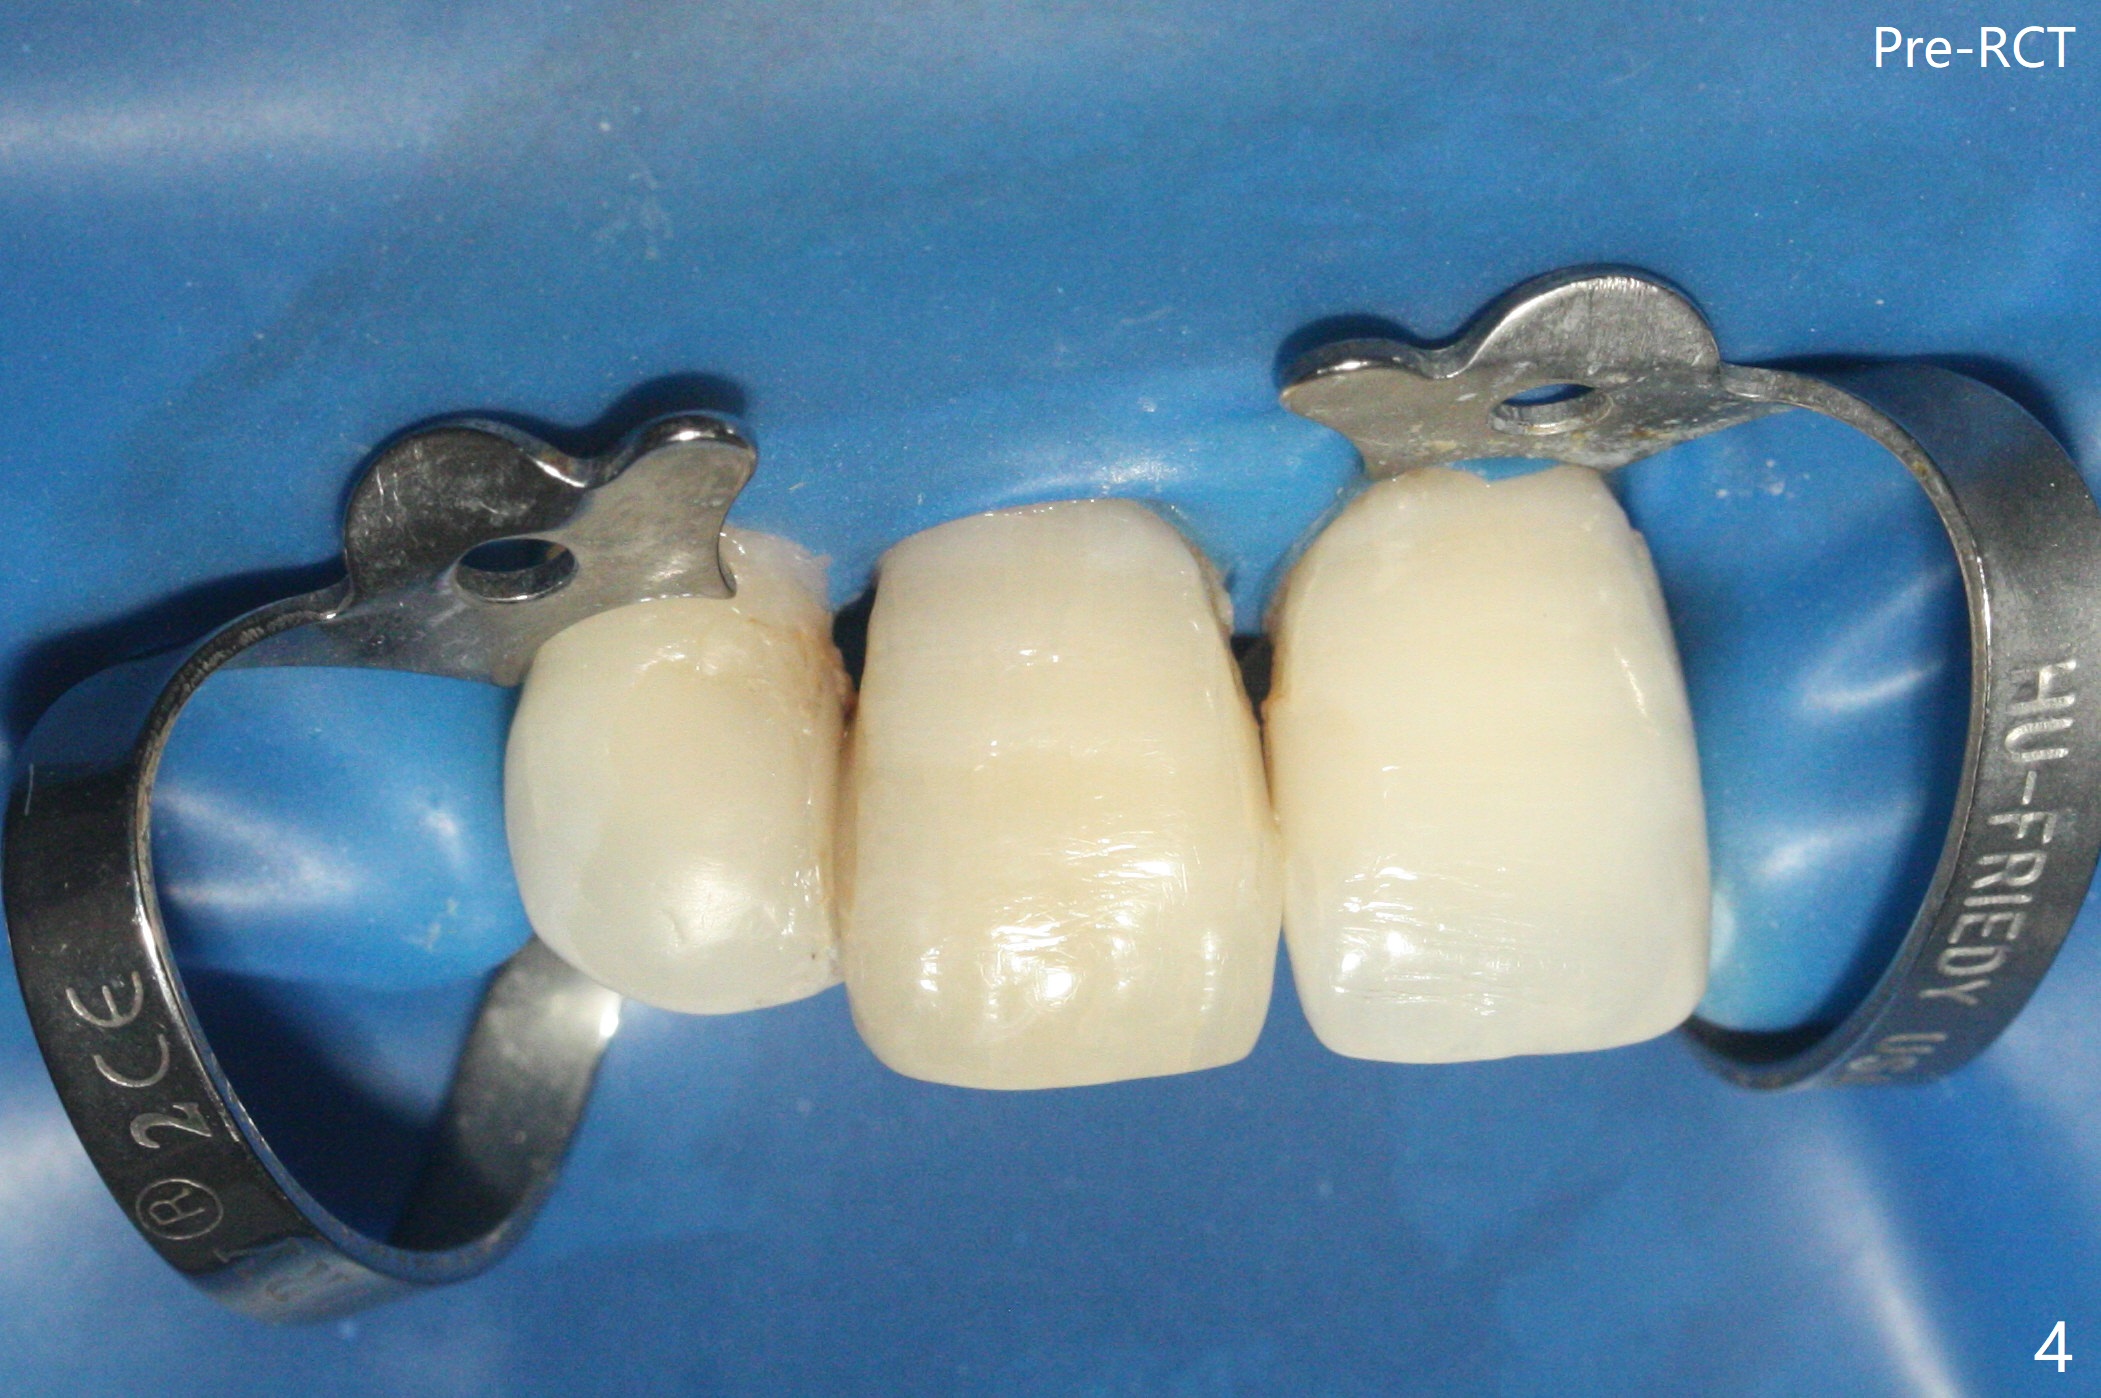

单个门牙变色往往是牙髓坏死所致,根管充填后做漂白,防止漂白泡沫跑到根尖孔之外,这种顺序可以改变吗?53岁女右上1根尖无痛性红肿(图一:^),牙冠变色(图二),牙髓测定:死髓,伴有根尖阴影(图三),中切牙需要根管治疗,什么时候漂白最好,步骤便利?根管治疗后做内漂白,必须把牙胶尖取出,釉牙骨质交界处之下,牙冠长,如这个病例,取出可能困难。我们准备尝试根管治疗当中做漂白,由于死髓牙,根管治疗可以不需要局麻,三个牙齿暴露在橡皮障之外(图四),以便术中漂白观察。根管治疗当中使用大量漂白水,好象并没有改善颜色(图五)。所以在根管口(图六)注入35%双氧水(漂白液,胶状),适当超越釉牙骨质交界处。万一双氧水气泡跑出根尖孔,我们将用生理盐水冲洗,不过这个意外没发生。双氧水也放置在患牙表面(外漂白),两次漂白后(每次20分钟),病人满意牙冠颜色改变(图七)。冲洗,擦干后,在根管中放置氢氧化钙糊剂。预约一个月后完成根管充填,如果牙冠颜色反弹,再次漂白。充填前需要多次冲洗,清除残余双氧水,后者抑制树脂固化。